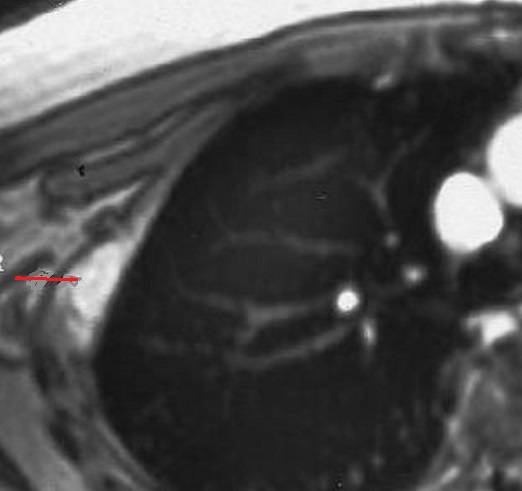

Espect metastatique de

tumefaction de la paroi thoracique droit et de

lyse de destruction osseuse correspondence du

côté droit d'une tumeur metastatique ( fleche rouge

) à origine de cancer pulmonaire ++ droit . Image

radiologique TDM en coupe axial |

Aspect radiologique de tumeur

metastatique secondaire de type mixte ( lysis et

condensant) multiple disseminé à des côtes du thorax

et à la colonne vertebrale . Image radiologique TDM

en coupe axial , fenêtre mediastinale |